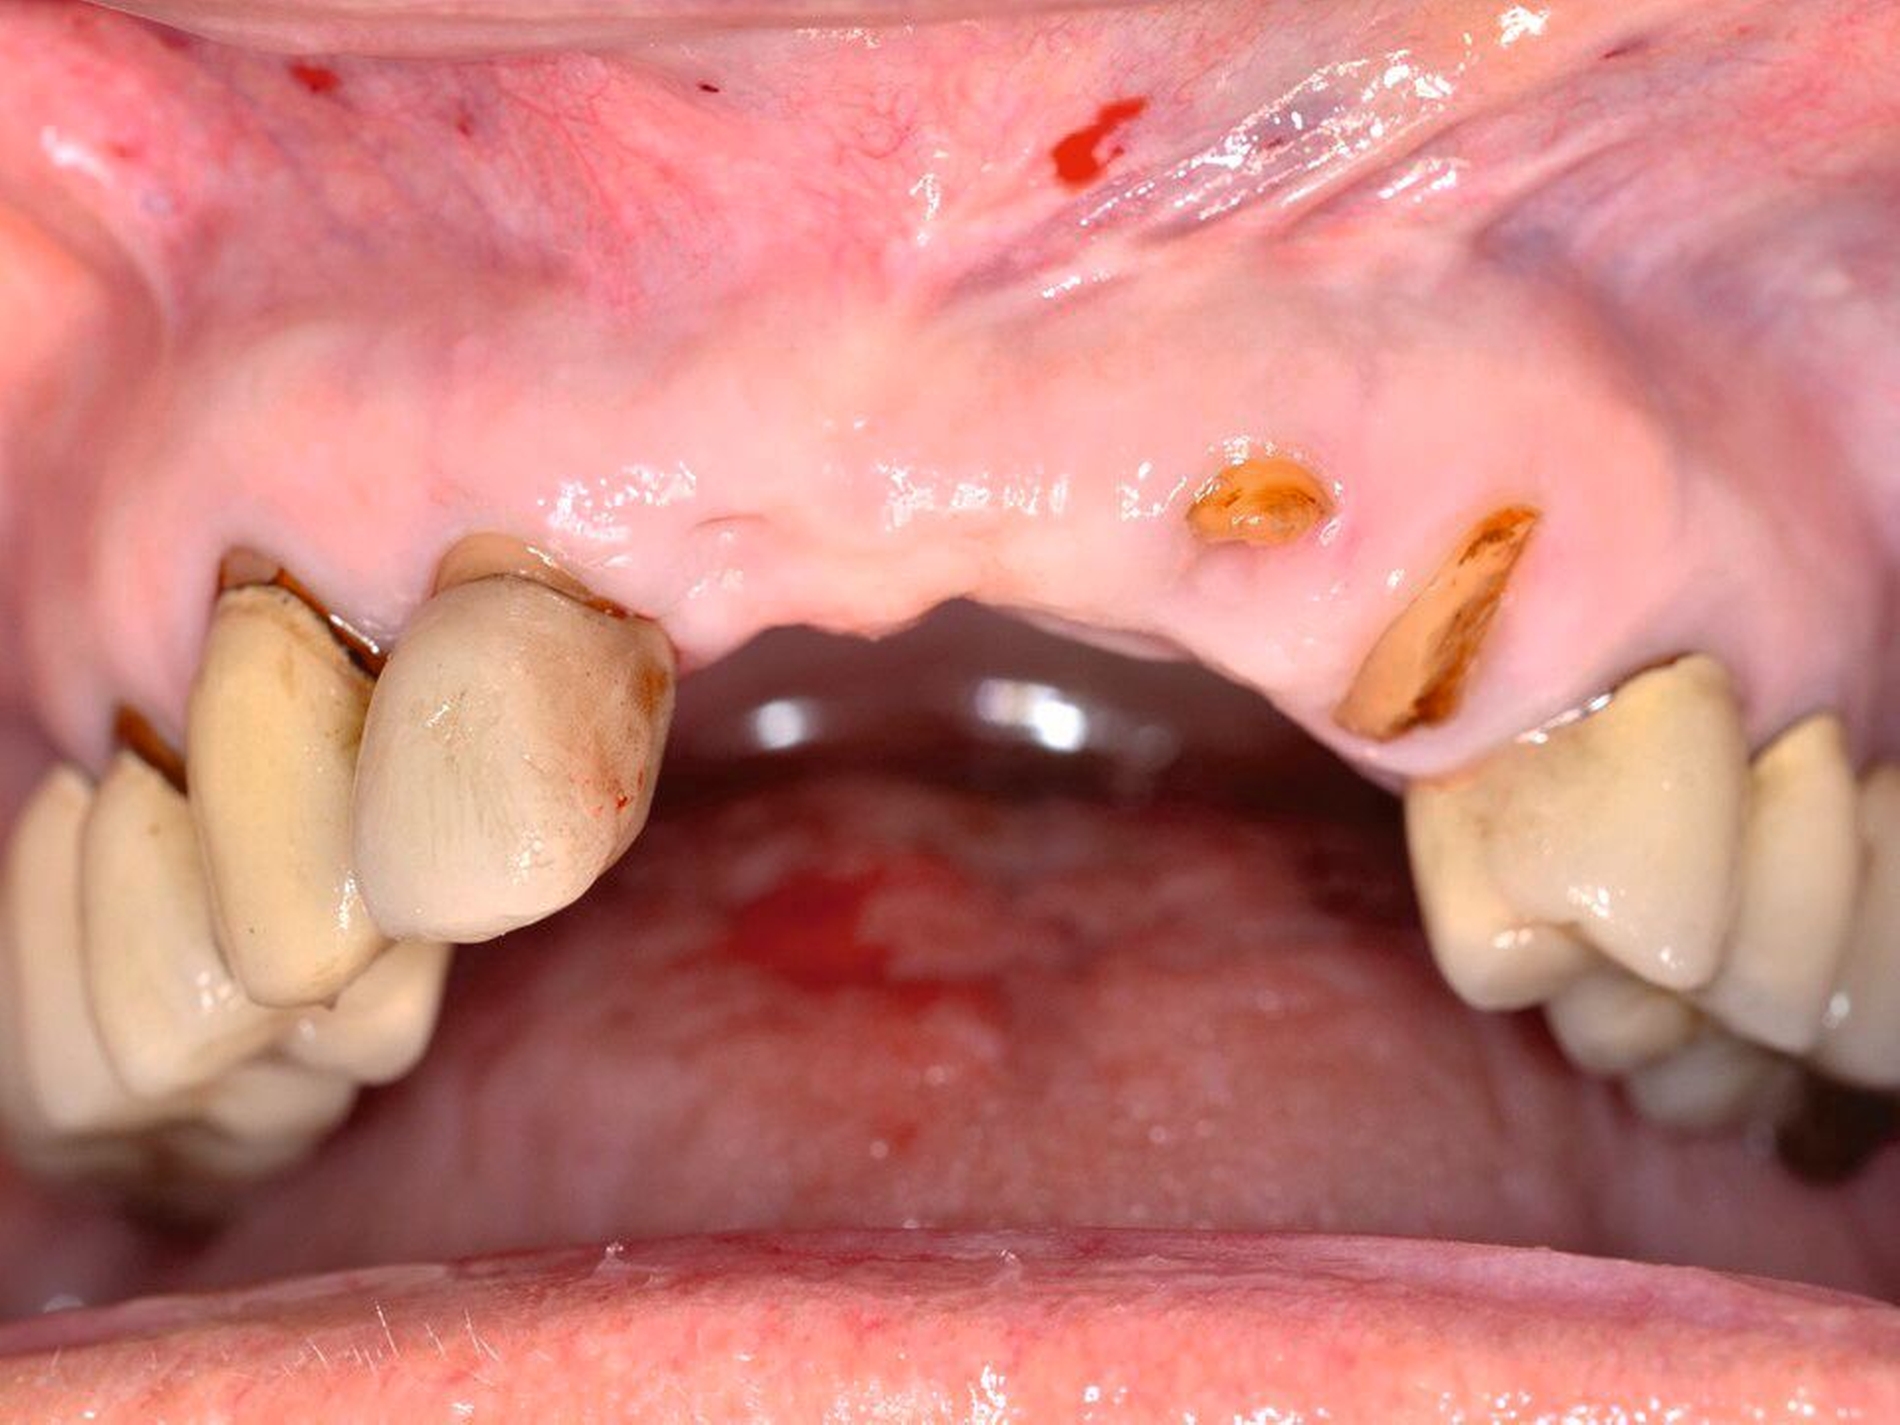

Die Versorgung einer Lücke mit Zahnimplantaten nach einem dentalen Trauma wird in der Regel nach Abschluss des pubertären Wachstumsschubes erwogen oder besser noch ins frühe Erwachsenenalter verlegt. Wenn zu diesem Zeitpunkt keine Sofortimplantation zusammen mit der Zahnwurzelextraktion erfolgt, sollte die Möglichkeit der Ridge preservation geprüft werden. Wenn eine Versorgung mit Zahnimplantaten erfolgt, dann nicht in der Akutphase des Traumas, sondern nach Abheilung der Weichteilwunden und der direkten allgemeinen Traumafolgen (Abbildung 5).